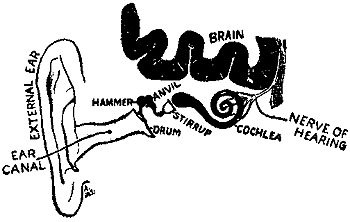

267 The Apparatus of Hearing

It is well to have the quality and purity of the milk tested just before it goes to the consumer, but it is far more important that it should be examined by State Inspectors at the dairy farms.